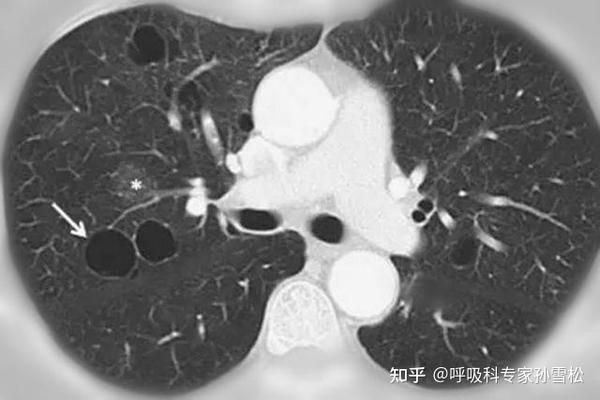

体检发现 肺大疱 怎么办 知乎

一文读懂肺大疱 湃客 澎湃新闻 The Paper